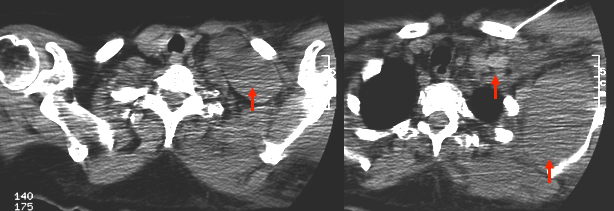

Die in der Anästhesie verbreitete Punktion der distalen Vena jugularis ist komplikationsträchtig und sollte vermieden werden. Normalerweise liegt die Vena jugularis lateral der A. carotis.

Bei der schädelnahen Punktion muß der Kopf nach links gedreht werden, weil sonst das Kinn im Weg ist. Dadurch rotiert die Vene vor die Arterie und das Lumen wird schlitzförmig.

Vor der Einmündung in die Vena anonyma macht die Jugularvene einen Knick von 45 Grad nach dorsal. Diatator, Einführschleuse und Katheter stoßen dort an der Venenvorderwand an und erzeugen Intimaläsionen, die bei 30% der Patienten später zur Thrombose führen.

Darüberhinaus geht der Katheter durch die ganze Breite des Musculus sternocleidomastoideus. Dies führt zu einer rein/raus-Bewegung des Katheters bei jedem Schlucken und jeder Kopfbewegung. Das begünstigt einerseits das Einwandern von Hautkeimen in den Punktionskanal, andererseits werden Fibrinablagerungen auf der Katheteroberfläche an der Punktionsstelle abgestreift. Dadurch kommt es zu einer Akkumulation von Fibrin und thrombotischem Material an der Venenwand und um den Katheter.

Von links eingeführte Katheter stoßen in der in mehreren Ebenen gewundenen Vena brachiocephalica an die Venenwand an und verursachen Intimaläsionen und Thrombosen. Die Wandschäden sind umso schlimmer, je steifer der Katheter ist. Die schlimmsten Schäden rufen die in der Intensivmedizin üblichen lage bore Katheter hervor.

-Intimaläsionen durch Druck des Katheters und ständige Bewegung an der Kathetereintrittsstelle verursachen Stenosen und Thrombosen bei 60% rechts bis 90% links ( M DeCicco, M Matovic, L Balestreri, G Panarello, D Fantin, S Morassut, V Testa: Central venous thrombosis: an early and frequent complication in cancer patients bearing long-term silastic catheter. A prospective study. Thrombosis Res. 1997;96:101-113.)

Bei diesem Patienten hat der Chirurg nicht nur auf die obligatorische Durchleuchtng verzichtet, sondern auch noch die ganzen 50 cm Plastikschlauch, die in der Packung sind, ungekürzt in den Patienten geschoben, obwohl der Abstand von der Punktionsstelle bis zur Cava/Vorhofgrenze, wo die Katheterspitze liegen soll, nur 10-12 cm beträgt. Dem Patienten wurden mehrere Zyklen Chemotherapie ins Hirn infundiert, bis die resultierende Sinusvenenthrombose zur Entdeckung der Fehllage führte.